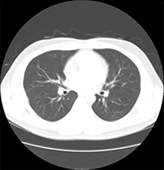

CT検査

CT(Computed Tomography:コンピュータ断層撮影)検査とは、体の周囲からX線を照射することによって断層(輪切り)像が得られる検査です。 CT検査の特徴として、通常のX線撮影などで検出されにくい小さな病変を見つけることができ、広範囲な撮影も可能です。造影剤を用いる事により血管の狭窄や閉塞、瘤の存在や形態を把握できます。また、タイミングを変えて(多時相)撮影することで、腫瘍の良悪性や広がりなどを詳しく調べる事ができます。薄いスライスの画像を重ね合わせて得られる3D(三次元立体)画像は、病変部と血管また骨などの位置関係を多方向から容易に把握できるので、診断や治療等へ活用されています。

当院のCT装置はSOMATOM Force (SIEMENS社製)及び 、Optima CT660 Pro (GE社製)の2台が稼動しており、通常は予約検査で行っておりますが、当日や緊急検査にも対応しています。肺がんを早期発見する為の肺検診では胸部CT検診学会の基準に則った低線量 (X線)で撮影しています。また、心疾患の診断、肺病変の性状を調べる為の肺生検、メタボリックシンドロームの指標となっている内臓脂肪量測定検査なども行っております。

肺CT1.25mm厚画像 画質を低下させずに、より低線量で撮像可能です。